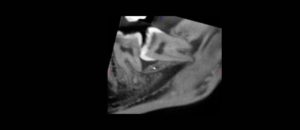

La compleja anatomía del sistema de conductos radiculares ha sido ampliamente estudiada, en esta ocasión nos enfocaremos en uno en particular, el CONDUCTO MEDIO MESIAL. Las